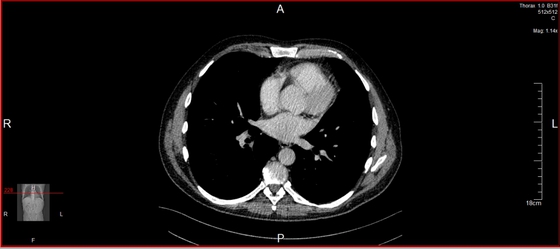

Me han hecho más pruebas que a un abducido por los marcianos de Roswell: desde escanearme en lonchas como a una barra de choppez a sacarme muestras de sangre suficientes como para completar la colección de Dexter.

¿Y qué tiene que ver todo esto con los viajes?, os preguntaréis algunos. Pues que si me hubiese puesto malo justo un mes y medio antes, me habrían tenido que ingresar de urgencias en algún hospital de Osaka o Tokio, por donde andaba de viaje. Como Japón no tiene acuerdo sanitario con España, ¿adivináis quién habría tenido que pagar el TAC, los electrocardiogramas, los hemocultivos, el ecocardio, la manutención y todas las pruebas que todavía me siguen haciendo?